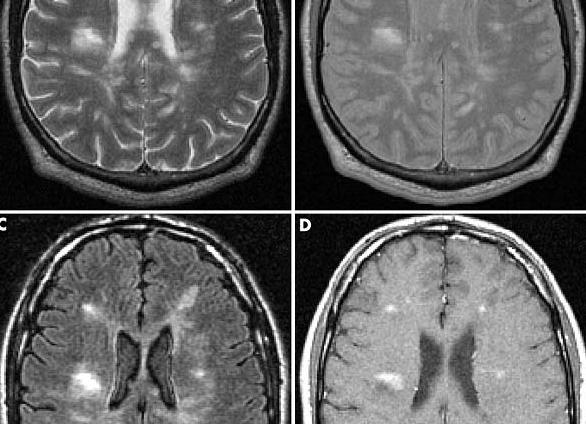

Признаки рассеянного склероза на МРТ хорошо видны специалисту. Для получения ясной картины на томографе делают снимок головного и спинного мозга в трех проекциях. Сами миелиновые оболочки нервов имеют вид своеобразных «муфточек», но видны они только под микроскопом. Однако на снимках МРТ при рассеянном склерозе видны бляшки в виде темных (на Т1-снимках) и светлых (на Т2-снимках) пятен. К тому же при достаточно обширном воспалении наблюдаются отеки, которые имеют свойство сливаться друг с другом, достигая в диаметре нескольких сантиметров.

Бляшки различны по размеру (более мелкие свидетельствуют о том, что заболевание началось недавно), по форме (более круглая означает острый склероз, овальная — хронический). Когда применяются контрастные препараты, медик смотрит на интенсивность изменения цвета — она может сказать о том, рецидивирует ли заболевание (в случае неравномерного окрашивания). Таким образом, рассеянный склероз на МРТ можно диагностировать с довольно высокой точностью.

Обычно рассеянный склероз на МРТ (большая часть очагов демиелинизации) располагается в белом веществе нервной системы: вблизи боковых желудочков, стволе головного мозга, семиовальном центре, височных долях и мозжечке. В меньшей степени поражаются отделы нервной системы, находящиеся на границе белого и серого, а также в сером веществе.

Существует несколько режимов визуализации очагов рассеянного склероза на МРТ-снимках.

На одном из таких (T1), участки демиелинизации выглядят темнее здорового мозгового вещества и показывают хронические очаги.

Т2-режим позволяет оценить объем поражения, в нем области демиелинизации выглядят белыми.

Очаги демиелинизации на томограмме головного мозга

В норме данные препараты не проходят гематоэнцефалического барьера, но при нарушении его целостности (как при этой патологии), контрастные вещества окрашивают очаги демиелинизации и делают их видимыми для исследователя. При введении контраста можно получить информацию даже об очень мелких очагах, недоступных для других методик. По уровню накопления контрастных веществ можно судить об активности заболевания, возможно отличить участки активного воспаления от участков затухания, а также от областей без активности.